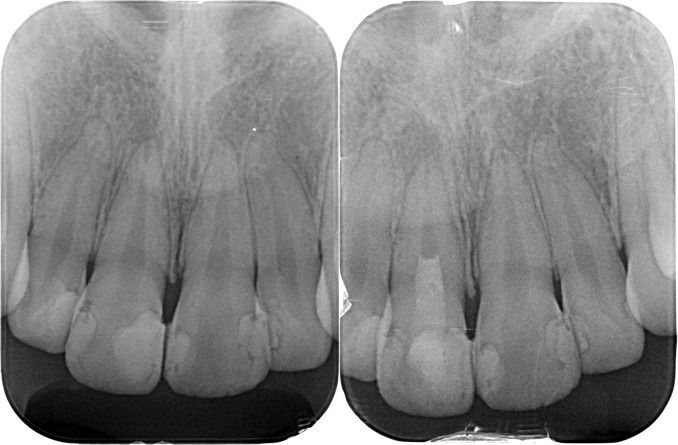

左:初診時 右:術直後

(図31)

左:当然根尖部の形態は初診時と変化なし

右:根尖部付近の形態に変化を確認できる

左:術直後 右:術後3ヶ月後

(図33)初診時と術後3ヶ月のレントゲン像の比較

根尖部付近に明らかに変化が認められる